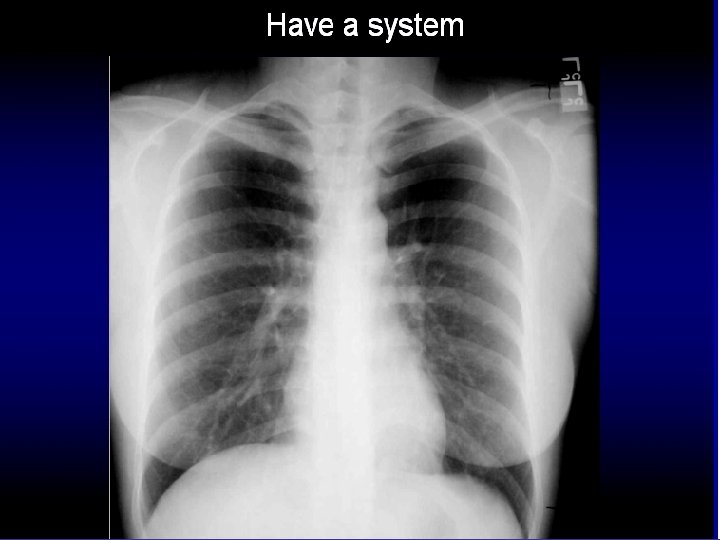

How do you look at chest x ray? Avoid tunnel vision

How to read a chest x ray ? • 1 - chest wall, bones

How to read a chest x ray ? • 1 - chest wall, bones and abdomen * bones; lesions or fractures * soft tissue ; mastectomy or soft tissue tumors • 2 - heart and mediastinum * trachea ; position & caliber * hila : lymphadenopathy * mediastinum contour : ? mass * heart : cardiac configuration • 3 - lungs opacity or lucency